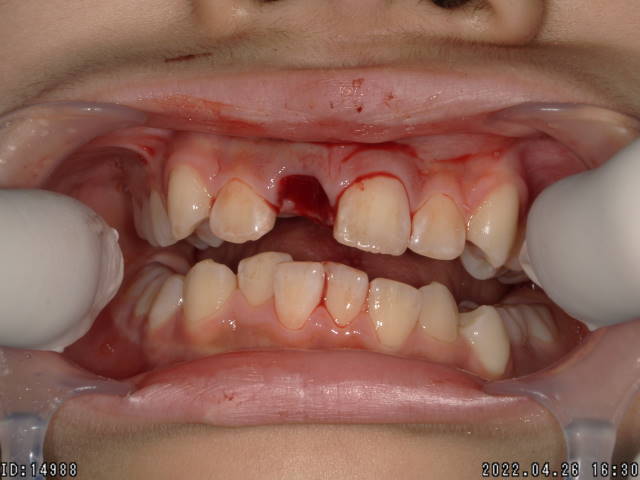

症例2

右上1番目と2番目の前歯は完全脱臼を起こし紛失してしまいました。

早期に再植すれば、生着する場合もあります。(歯牙の再植術)

他の歯牙も不完全脱臼していたため、矯正用の器材を使用して固定しました。